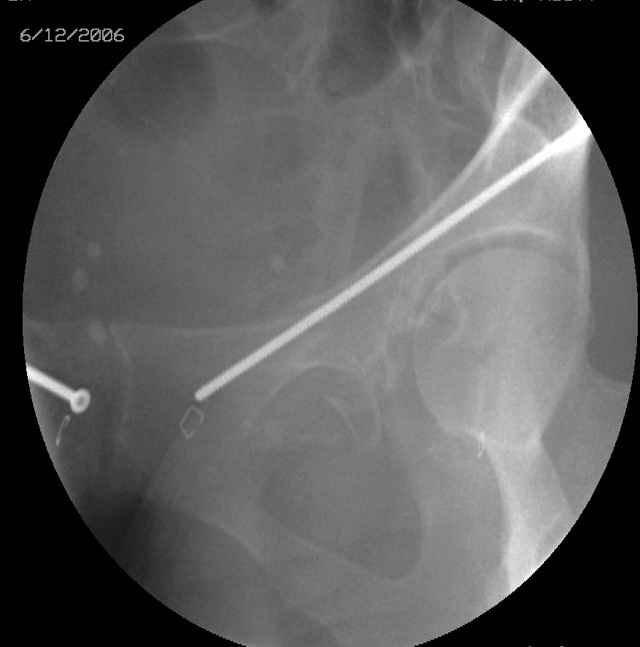

Prone Obturator-Outlet

Screw insertion using the obturator-outlet combination image.

12.Prone Obturator-Outlet

Same with a contoured pelvic reconstruction plate applied and tensioned.